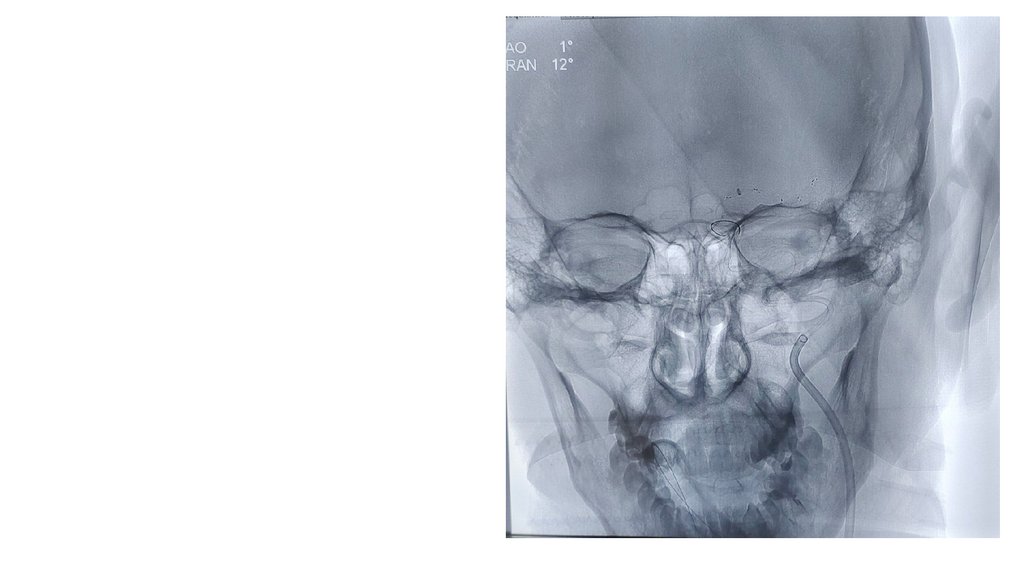

КТ-признаки острого

ишемического инфаркта в

бассейне левой средней

мозговой артерии

(ASPECTS 7).

Тромбоз ВСА-СМА слева?

Патологии костей свода и

основания черепа не

определяется.

КТ АГ: Вероятнее, окклюзия левой ВСА на

уровне С3-4.

Больному показано проведение ВСТЭ.

Ангиографический диагноз: острая

окклюзия ЛВСА слева.